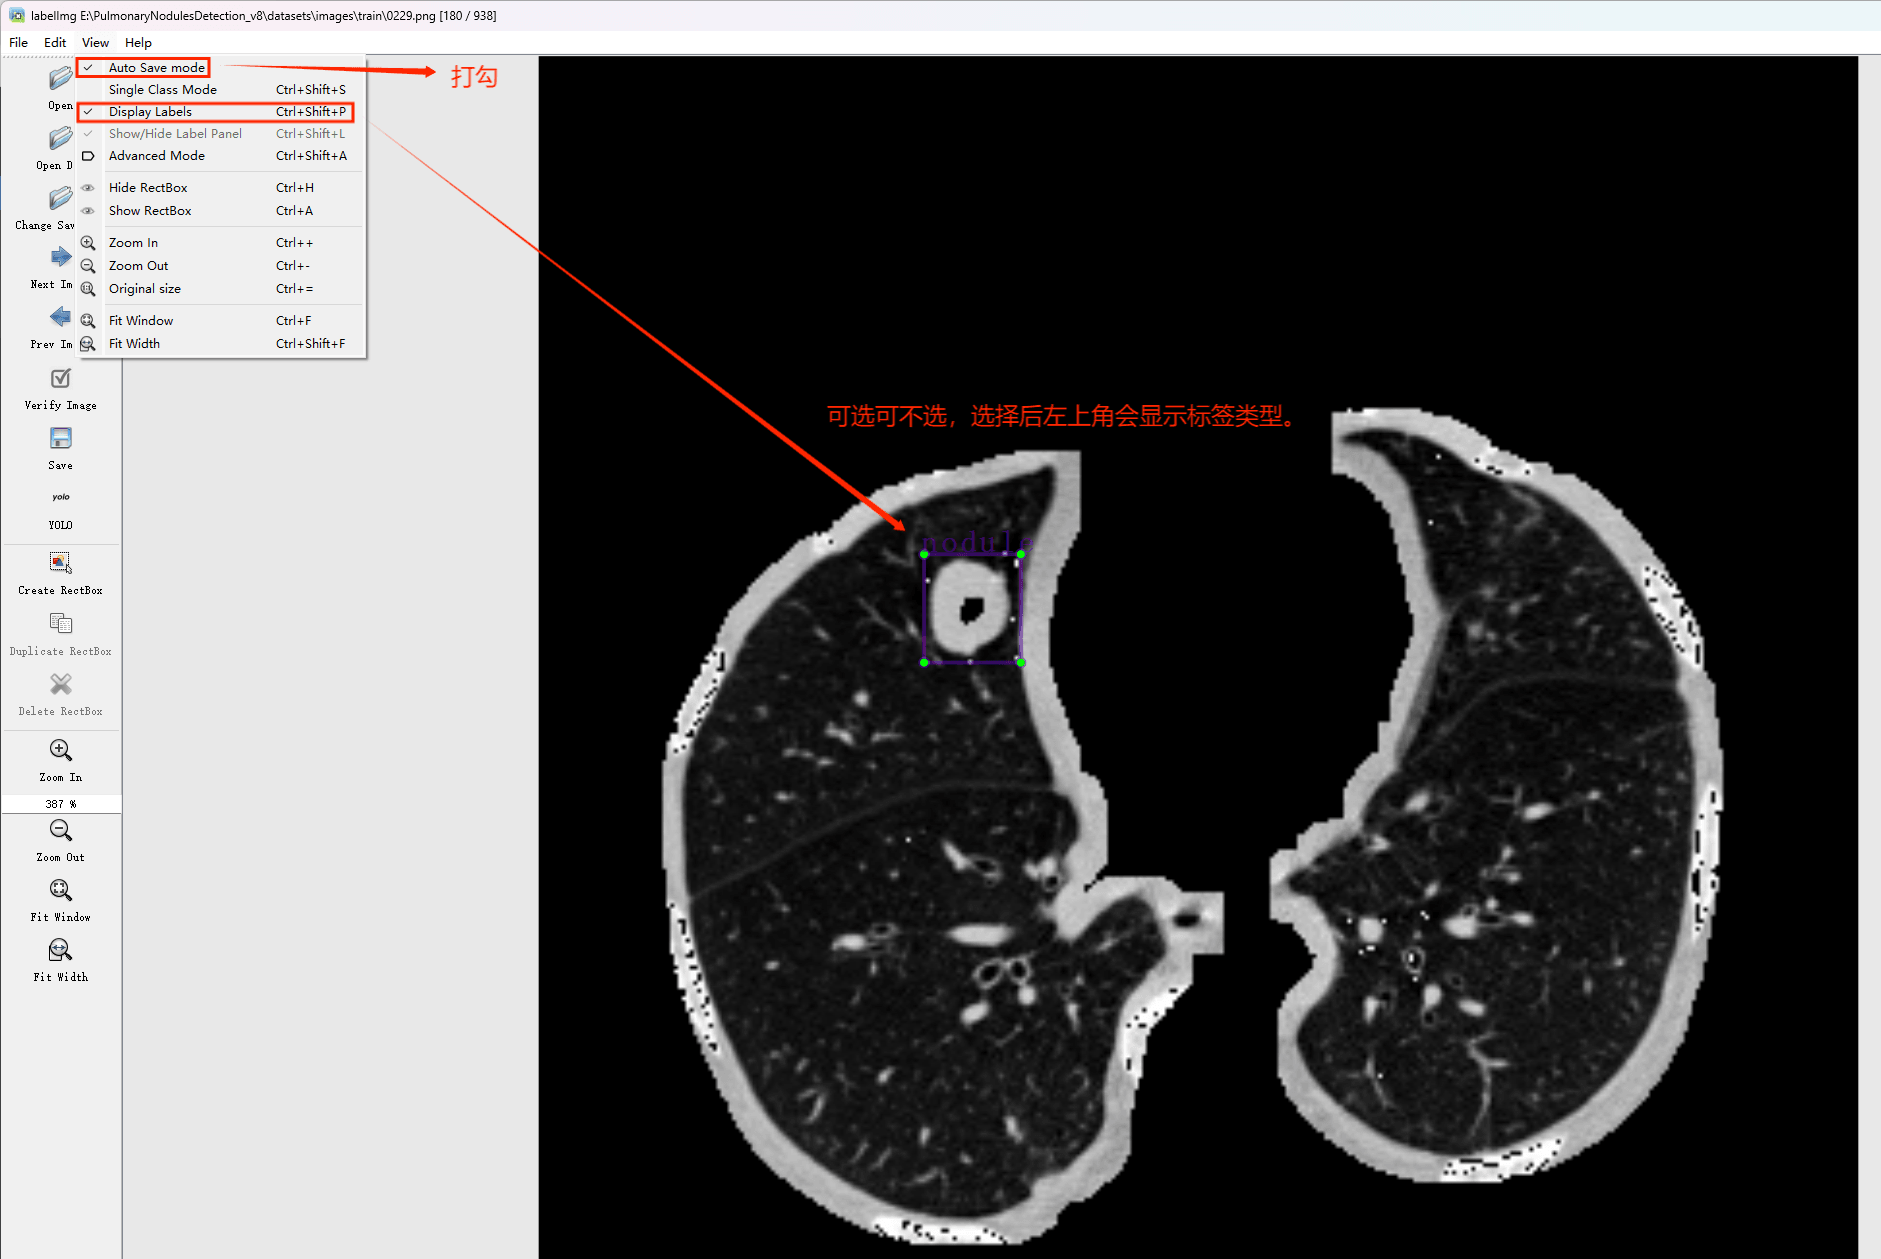

目标检测标注工具

(1)labelimg:开源的图像标注工具,标签可用于分类和目标检测,它是用python写的,并使用Qt作为其图形界面,简单好用(虽然是英文版的)。其注释以 PASCAL VOC格式保存为XML文件,这是ImageNet使用的格式。此外,它还支持 COCO数据集格式。

(2)安装labelimg 在cmd输入以下命令 pip install labelimg -i https://pypi.tuna.tsinghua.edu.cn/simple

初识labelimg

打开后,我们自己设置一下

在View中勾选Auto Save mode

接下来我们打开需要标注的图片文件夹

并设置标注文件保存的目录(上图中的Change Save Dir)

接下来就开始标注,画框,标记目标的label,然后d切换到下一张继续标注,不断重复重复。